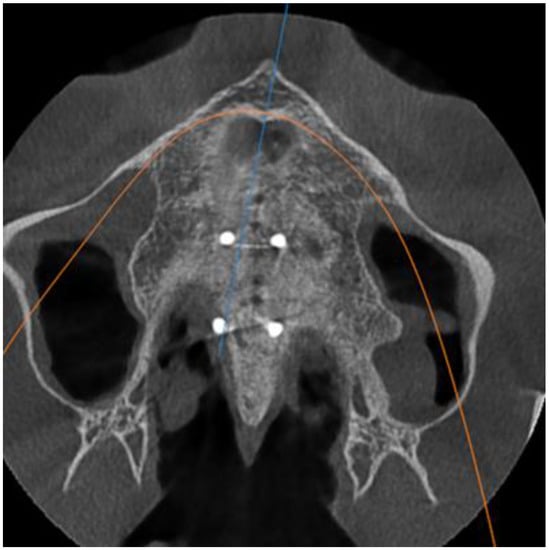

- Stage D or E palatal fusion (as seen in Angelieri et al. [18]) confirmed on CBCT prior to MARPE insertion;